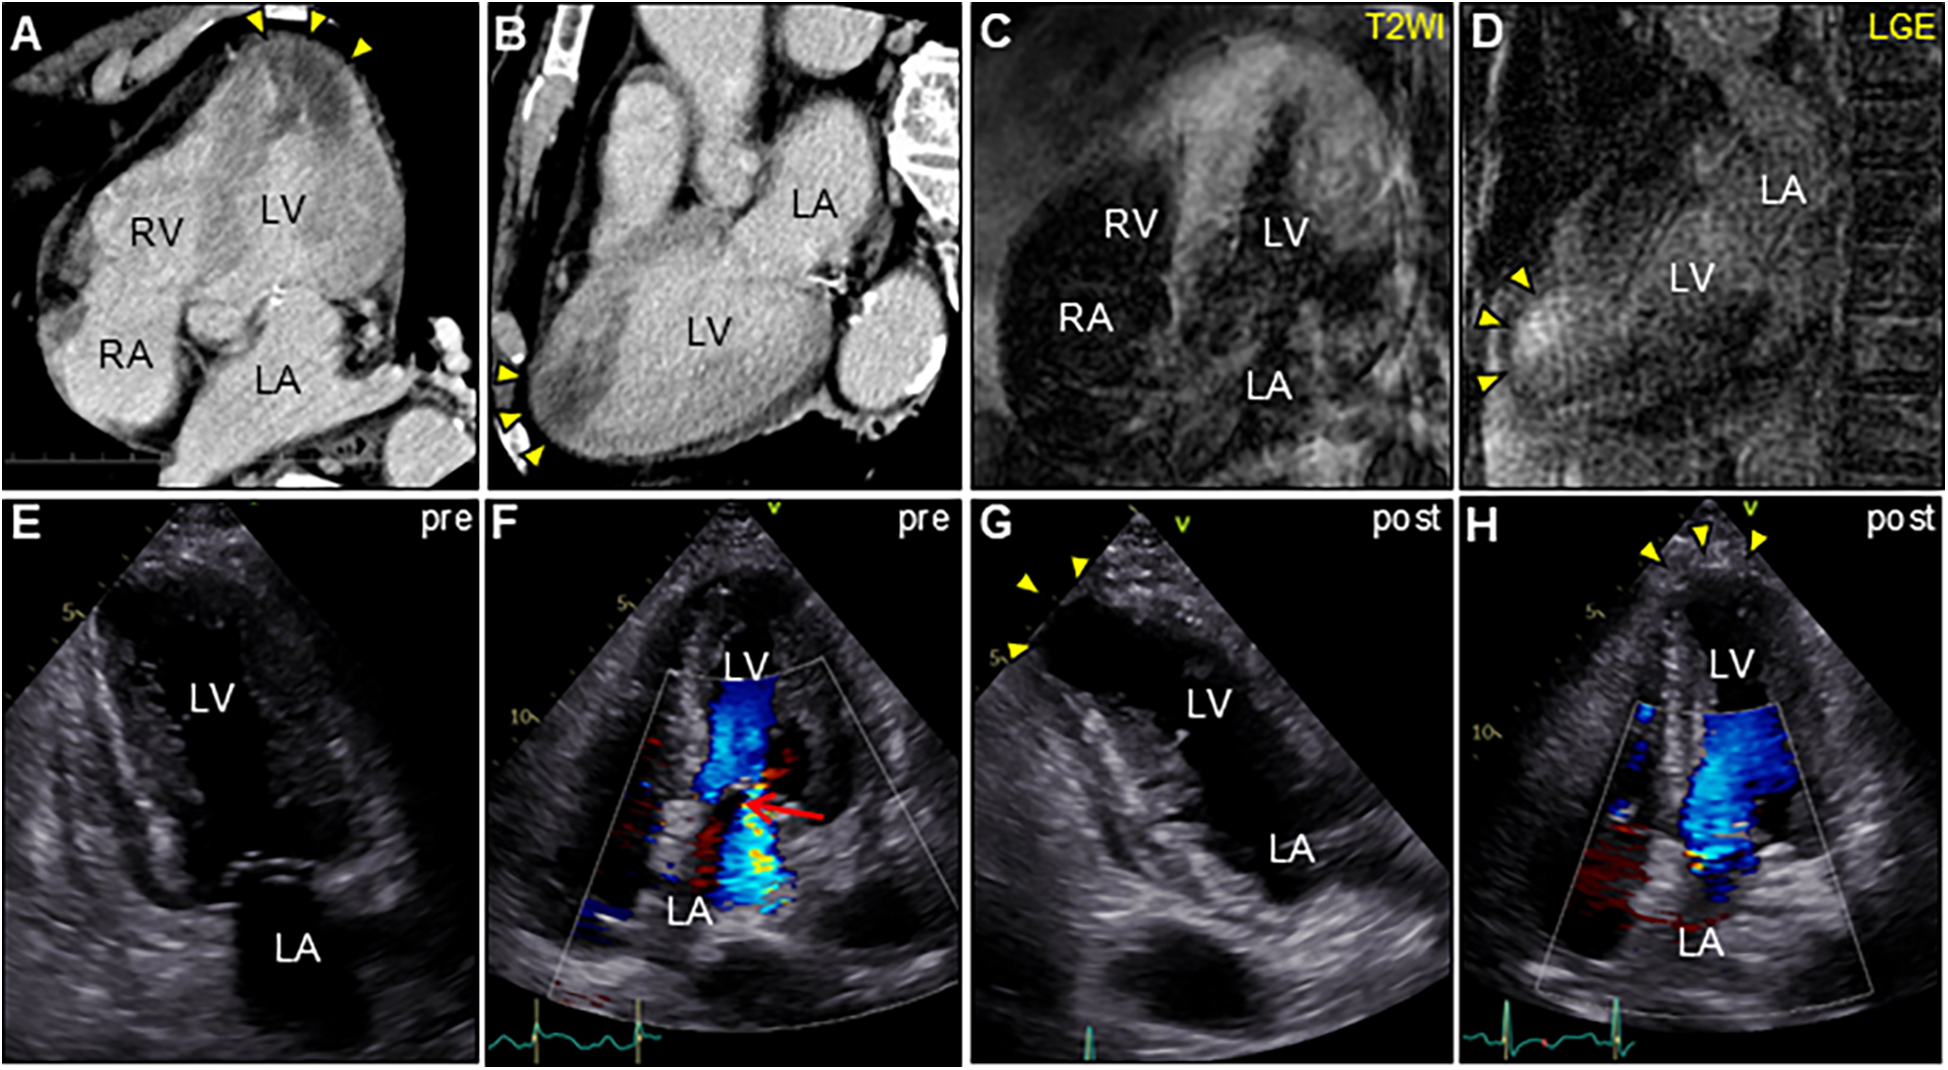

Figure 2. Enhanced computed tomography (CT) and cardiac magnetic resonance imaging (CMR) (A,C, apical four-chamber view; B,D, long-axis view). CT showing low-attenuation areas of the left ventricular apex (arrowheads). T2-weighted image (T2WI) showing diffuse myocardial edema. Late gadolinium enhancement (LGE) images showing the same region as that of CT (arrowheads). Serial transthoracic echocardiography (TTE). (E,G, apical two-chamber view; and F,H, apical four-chamber view). (E,F) TTE on day 6 after admission showing severe global left ventricular systolic dysfunction with increased left ventricular wall thickness (LVWT) accompanied by severe mitral regurgitation (arrow) in color Doppler mode [LVWT, 14 mm; and ejection fraction (EF), 40%]. (G,H) Follow-up TTE 2 weeks after corticosteroid treatment showing considerable improvement in left ventricular function and mitral regurgitation (LVWT, 12 mm; and EF, 57%). Note the left ventricular apical aneurysmal formation (arrowheads). LA, left atrium; LV, left ventricle; RA, right atrium; RV, right ventricle.

An 85-year-old man with high-grade fever, nausea, fatigue, and urinary disturbance was admitted to our hospital. The patient had a history of hypertension and benign prostatic hyperplasia, but no history of autoimmune gastrointestinal disorders. His vital signs were as follows: blood pressure, 160/102 mmHg; heart rate, 99 beats/min; and body temperature, 38.2°C. A physical examination revealed a distended abdomen. Abdominal computed tomography (CT) revealed an enlarged prostate gland with a distended bladder wall and bilateral hydronephrosis, suggesting a urinary obstruction. Empirical antimicrobial treatment with intravenous ceftriaxone was initiated for suspected urinary tract infection. On day 2, the patient became agitated, disoriented, and unable to follow instructions. Neurological examination revealed left hemiparesis and profound bilateral hearing loss. Electrocardiography showed atrial fibrillation with tachycardia and ST-segment elevation in the precordial leads (Figure 1A). Brain magnetic resonance imaging (MRI) revealed multiple cerebral emboli and bilateral acute otitis media (AOM) (Figures 1B–D). Laboratory tests revealed a white blood cell count of 6,200/μl without eosinophilia and an elevated C-reactive protein (CRP) level of 7.47 mg/dl (normal: <0.3 mg/dl). Additionally, elevated levels of serum cardiac troponin I (cTnI; 11,023 pg/ml, normal: <26.2 pg/ml) and N-terminal pro-brain natriuretic peptide (NT-proBNP; 885 pg/ml, normal: <125 pg/ml) were observed. Coronary angiography and left ventriculography were unremarkable (Figure 1E). Echocardiography revealed left ventricular (LV) hypertrophy, preserved LV contraction, and mild pericardial effusion. Enhanced CT indicated acute myocardial edema of the LV apex involving the anterolateral pupillary muscle (Figures 2A,B). Cardiac MRI established acute myocarditis (Figures 2C,D). The repeated urine and blood cultures remained sterile. The fever and inflammatory response without leukocytosis raised the suspicion of acute viral myocarditis with concomitant cardiogenic emboli. The patient underwent close telemetric monitoring with intravenous heparin infusion, followed by oral anticoagulant and anti-heart failure treatment. Furthermore, acetaminophen was administered for AOM. On day 6, the patient was transferred to the intensive care unit (ICU) due to cardiogenic shock, requiring intubation and catecholamine support. Follow-up electrocardiography revealed pathological Q waves with complete ST-segment resolution. Follow-up echocardiography revealed severe diffuse global hypokinesis with severe mitral regurgitation (Figures 2E,F; Supplementary Videos S1 and S2). Follow-up laboratory examinations revealed a greater increase in serum cTnI (18,946 pg/ml), NT-proBNP (35,000 pg/ml), and CRP (10.08 mg/dl) levels. Note the transient increase in the circulating absolute eosinophilic count to 542 cells/μl (Supplementary Figure S1). Repeated left ventriculography confirmed reduced global systolic function with an ejection fraction of 35%, followed by the insertion of an intra-aortic balloon pump (IABP). Subsequent endomyocardial biopsy (EMB) revealed numerous eosinophilic infiltrations admixed with CD3+/CD4 + helper T lymphocytes, macrophages, and adjacent cardiomyocyte injury (Figures 3A, B, D–F). Immunostaining for major basic proteins demonstrated extensive staining, predominantly eosinophils in the endocardium (Figure 3C), with macrophage polarization toward the M2 phenotype (Figures 3G,H). These findings confirmed a definitive diagnosis of acute eosinophilic myocarditis (AEM), which was treated with intravenous methylprednisolone (1 g/day for 3 days), followed by oral prednisolone (1 mg/kg/day) with gradual dose tapering. Thereafter, the patient remained hemodynamically stable. The IABP was weaned off on day 12, and the patient was transferred from the ICU to the general ward.